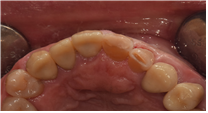

# 21, 22 치경부 마모증이 심하고 사이 충치까지 존재해 크라운 치료가 제일 심미적이겠지만, 필요한 부분만 제거하고 레진수복치료를 하였습니다.

#21.22 C.RF 절단면 RF 설명드림.

치료 전